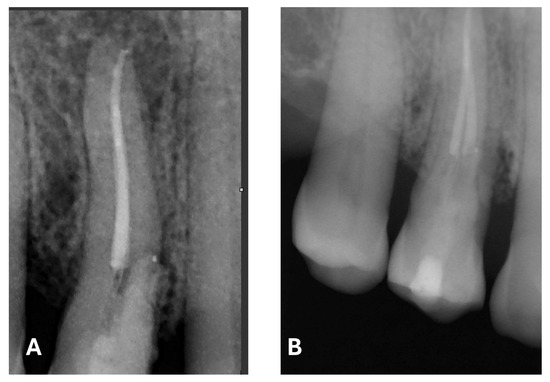

Figure 9.

Post-treatment radiograph with composite filling. (A) focus on the periapical lesion, root canal obturation and Biodentine application. (B) focus on composite filling. Note the radiographic evidence of widening of the lamina dura in the mesiocervical region.

The radiographic quality of endodontic treatment—particularly in regard to canal filling density, appropriate taper, and respect for the working length—is significantly associated with a lower incidence of endodontic failure. Inadequate fillings, overextensions, underfillings, or the presence of voids within the canal have been correlated with a higher likelihood of persistent periapical lesions and a reduced treatment success rate [25].

At the 12-month radiographic follow-up, healing of the EPL was confirmed. Restoration of the lamina dura and the periodontal ligament adjacent to the treated site was observed (Figure 16 and Figure 17).

Figure 16.

Intraoral radiography of tooth 1.4 at 12-month follow-up.